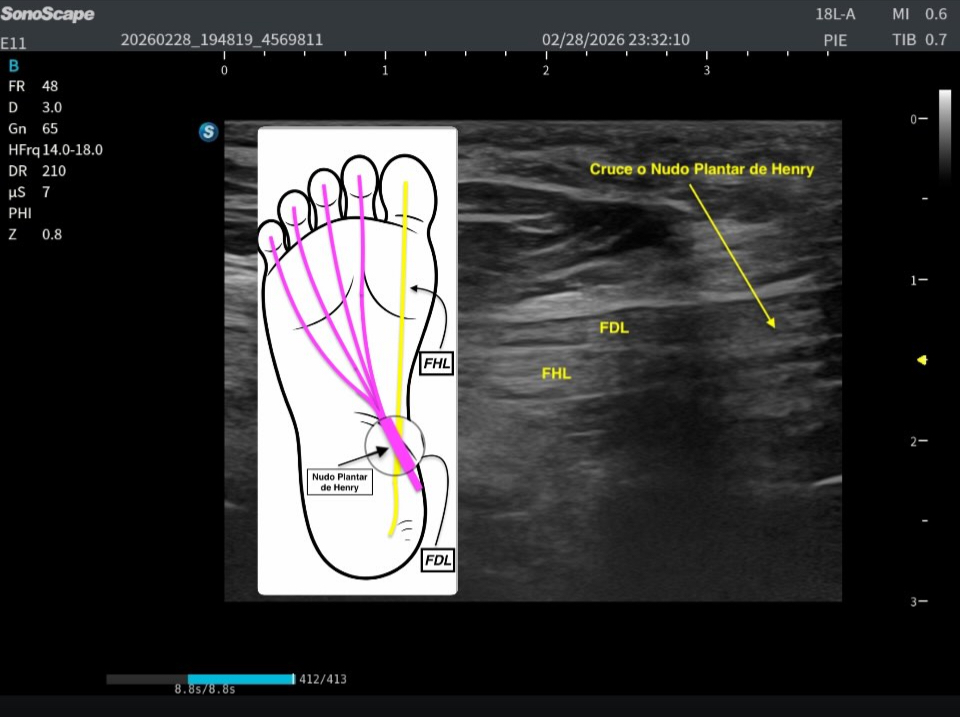

El flexor largo del primer dedo (FHL), en amarillo, se origina en la cara posterior del peroné y desciende por la región medial del tobillo, pasando por detrás del maléolo medial. Desde ahí continúa hacia la planta del pie para insertarse en la falange distal del hallux. Por su parte, el flexor largo de los dedos (FDL), en morado, se origina en la cara posterior de la tibia, también atraviesa la región medial del tobillo y desciende hacia la planta, donde se divide en cuatro tendones destinados a los dedos segundo a quinto.

En la porción profunda y medial de la planta del pie se produce un punto anatómico clave: ambos tendones se cruzan. Este cruce es lo que se conoce como nudo plantar de Henry. Es fundamental comprender que este entrecruzamiento ocurre en un plano profundo y que ambos tendones llegan a esa zona desde la región interna del tobillo.

Existe un detalle anatómico determinante que debemos tener muy claro: en el punto exacto del cruce, el FHL es profundo al FDL. Es decir, el tendón del primer dedo queda situado por debajo del tendón de los dedos largos. Esta relación espacial es constante y resulta esencial para la correcta interpretación ecográfica.

En esta localización exacta se demuestra de forma precisa el cruce de ambos tendones, que corresponde al nudo plantar de Henry. Justo debajo, en la imagen situada bajo este texto, se representa la misma región tanto en ecografía como en su correlación anatómica, facilitando la comprensión espacial del entrecruzamiento.

En la imagen inferior se aprecia perfectamente la correlación anatómica con la ecoestructura de ambos tendones, estudiados exactamente en esta zona y en corte longitudinal. Esta imagen es completamente extrapolable a la imagen superior obtenida en axial, ya que ambas representan el mismo punto anatómico: el nudo plantar de Henry, visualizado en planos diferentes pero complementarios.